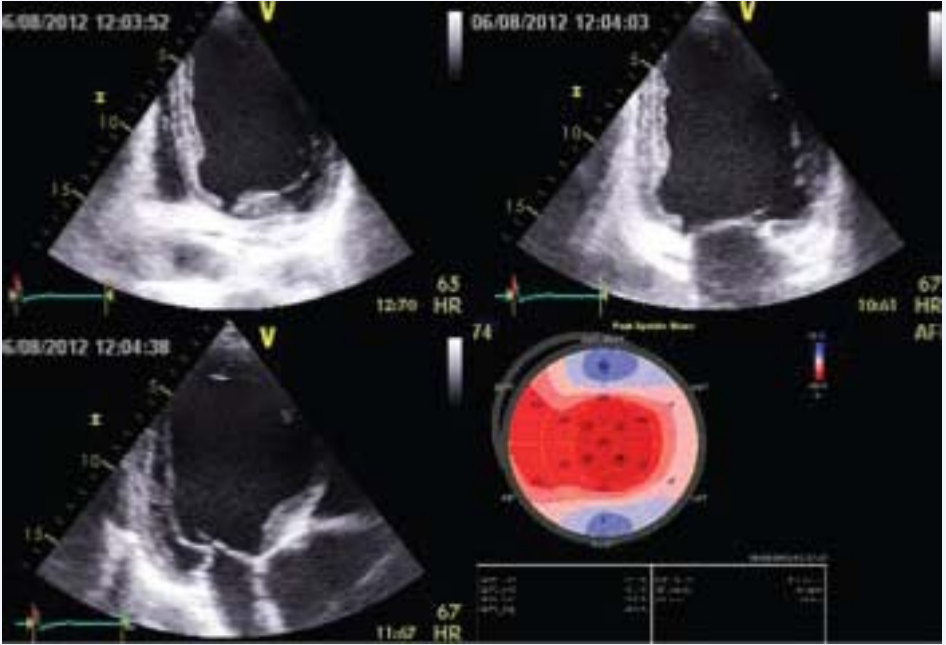

with the following 2D measures: aortic ring = 4.1 cm, Valsalva sinuses = 5.18 cm, sino-tubular junction = 7.1 cm and ascending aorta = 8.7 cm. The left ventricle was enlarged, with ejection fraction (calculated by Simpson’s method and using 3D software) of 41% and global longitudinal strain of -14.4% (Figure 3).

Global longitudinal strain of left ventricle.

Figure 3: Global longitudinal strain of left ventricle.